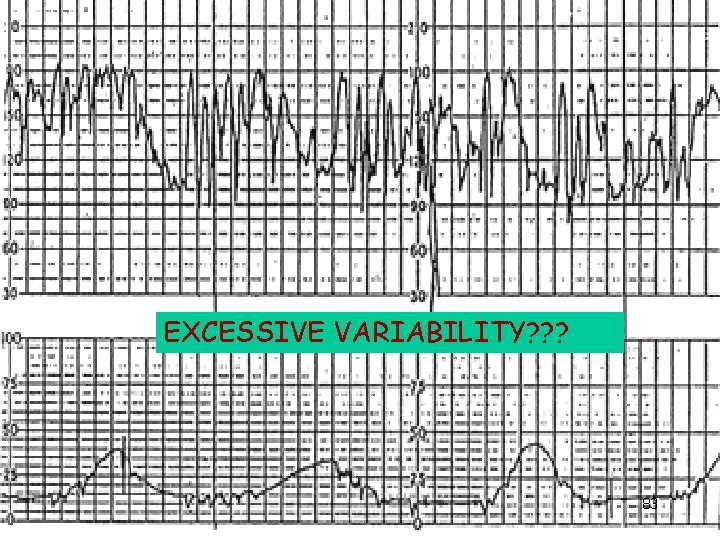

EXCESSIVE VARIABILITY? ? ? 83